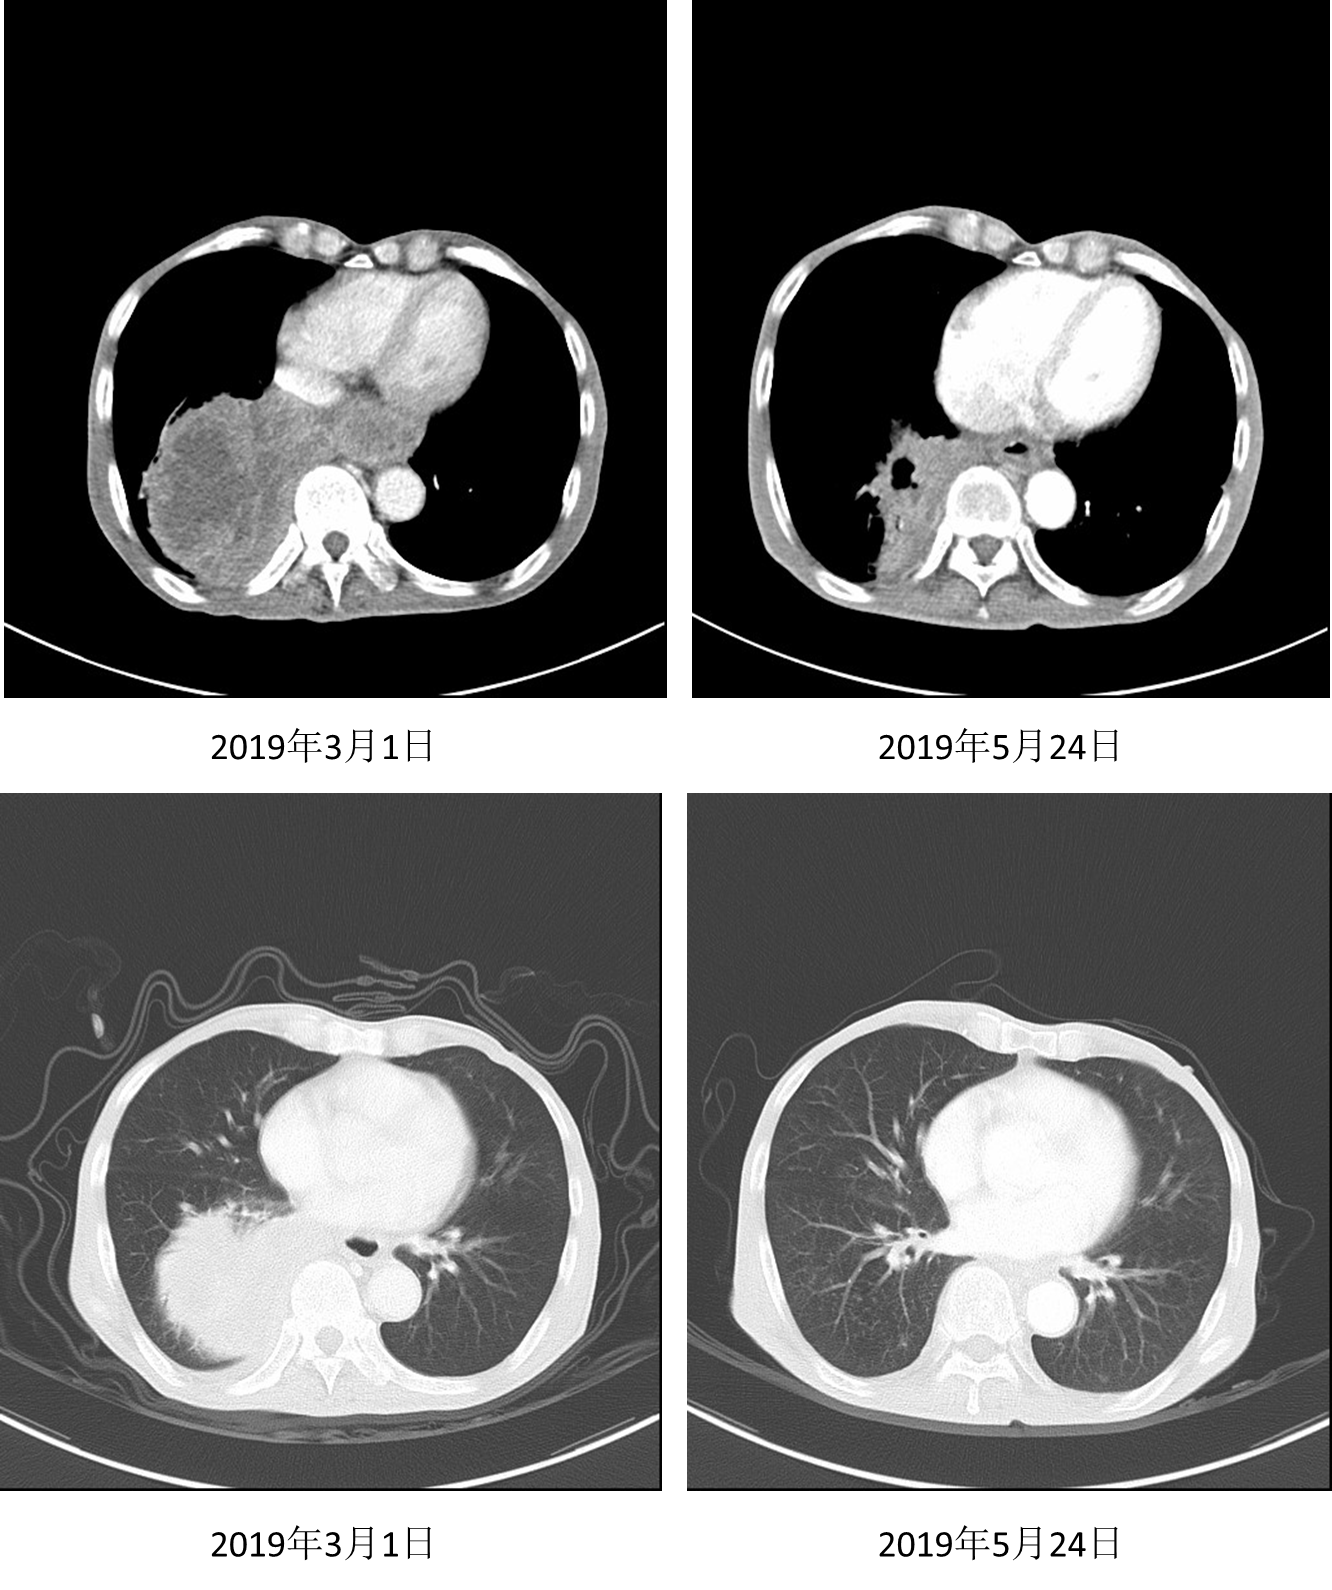

2018年12月至2月接受安罗替尼12mg/d治疗3个月;2019年3月1日复查,胸部肿块较前增大,且胸闷闭气症状加重,评价为疾病进展(PD)。

image005.png

图3. 2019年3月1日胸部CT